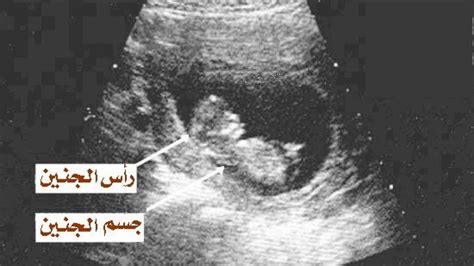

شكل الجنين في الأسبوع السابع بالموجات فوق الصوتية

- في هذه المرحلة، يبدأ طفلك الصغير في النمو جيدًا ويقدر طوله بحوالي تسعة إلى عشرة ملليمترات.

- وهنا نلاحظ شكل الجنين في الأسبوع السابع عن طريق الموجات فوق الصوتية حيث تبدأ أصابع يده وساقه في التكون.

- خلال هذا الوقت، قد لا تتمكنين من رؤية شكل الجنين في الأسبوع السابع بكل هذه التفاصيل الصغيرة على الموجات فوق الصوتية.

- بعد ذلك، في الأسبوع السابع، يظهر التطور الثالث عن طريق الموجات فوق الصوتية على شكل جنين، يُعرف باسم قطب الجنين.

- يمكن رؤيته من بداية الأسبوع السادس وغالبًا ما يكون مستطيلًا أو منحنيًا قليلاً.

- نجد أن لونه يظهر في السونار على شكل أبيض صلب أو سميك قليلاً.